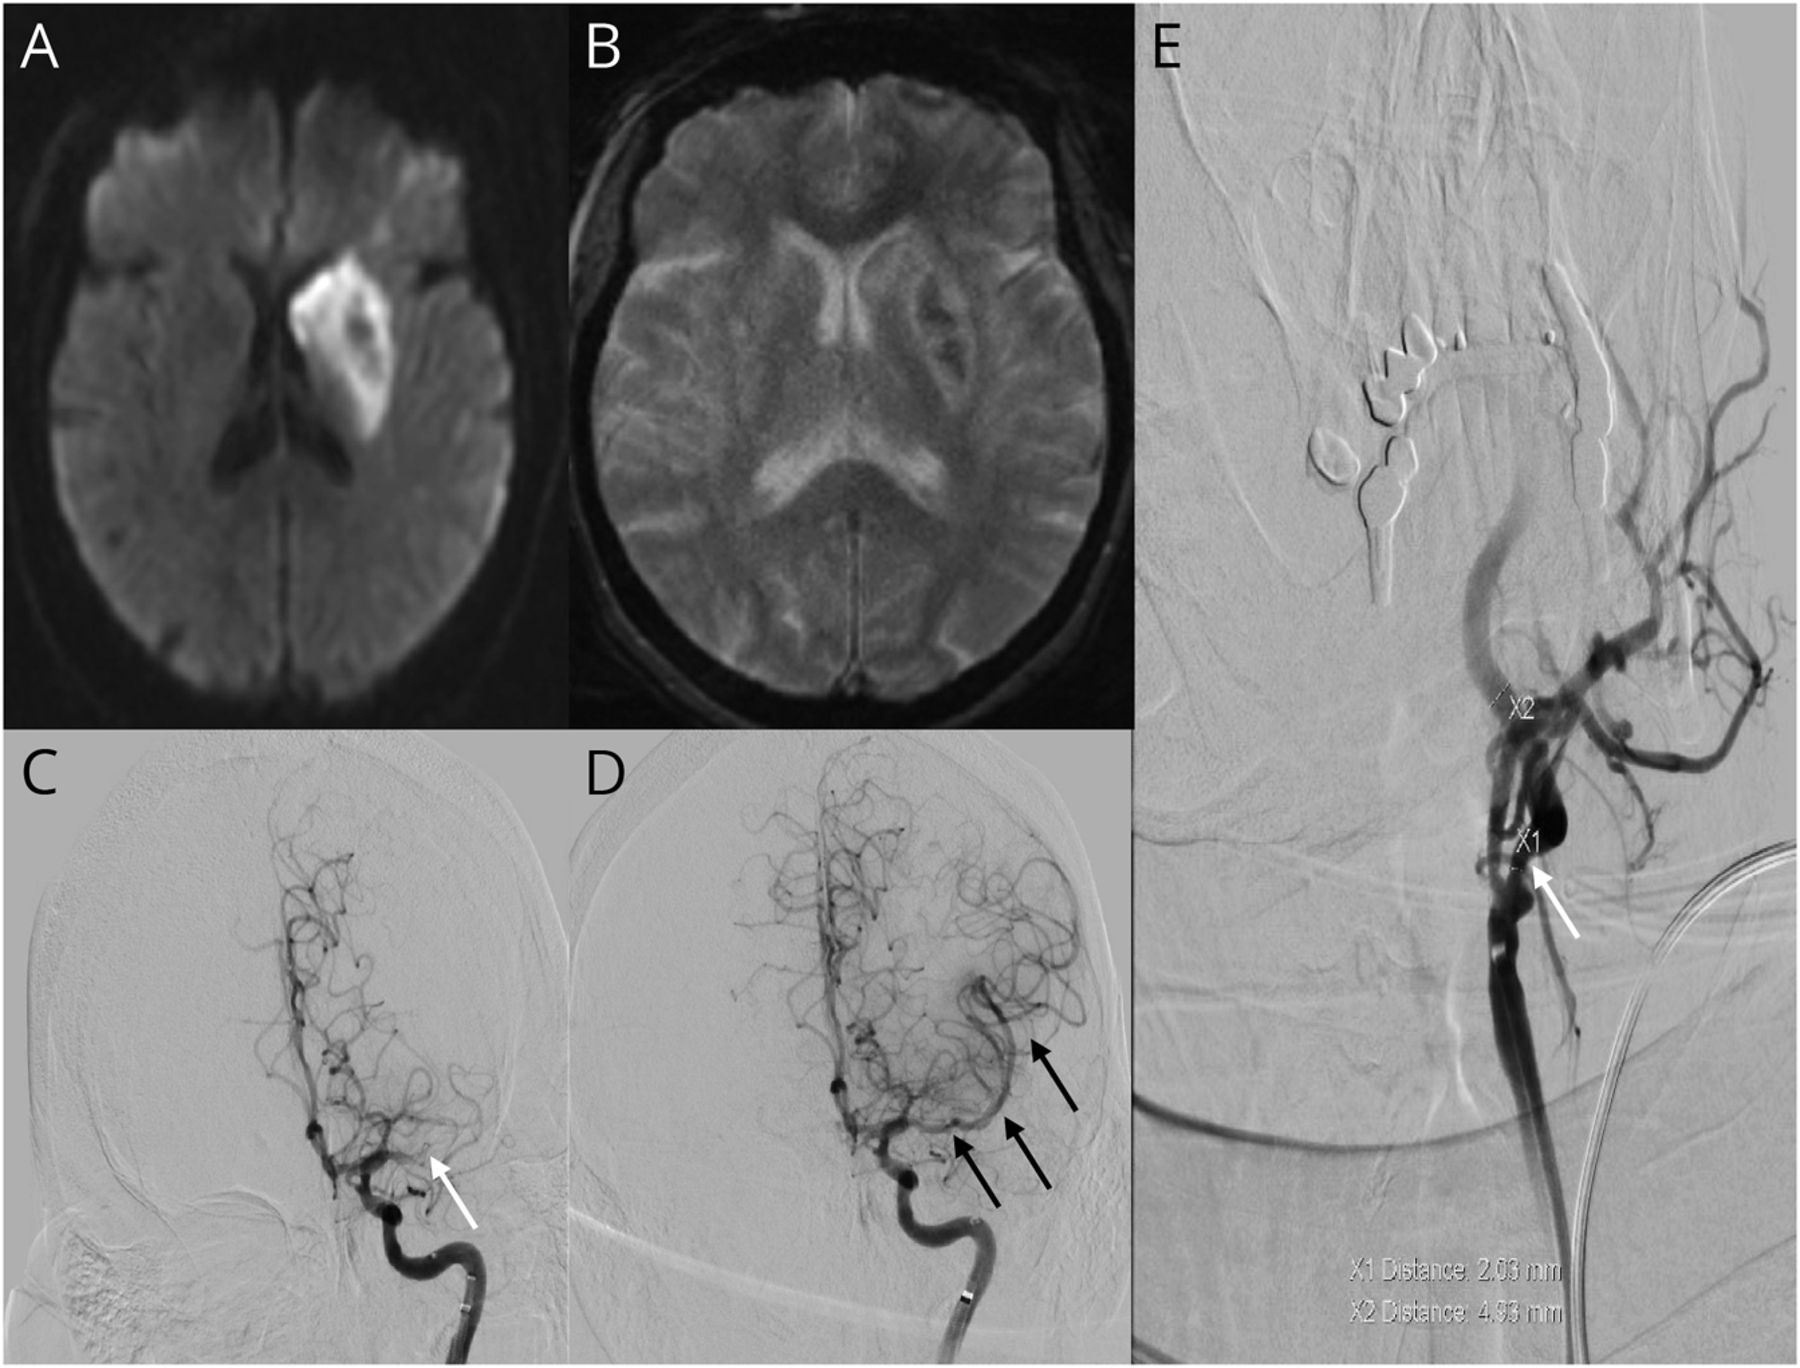

一个66岁的老妇人被带到我们的三级医疗中心后发现了一个未知的时间。她的病史是著名的为高血压、高脂血症、非胰岛素依赖糖尿病和之前的烟草使用。大脑的核磁共振显示区域的扩散限制涉及左侧尾状核和豆状核与瘀斑的出血性转换(图1中,A和B)。先生血管造影和灌注成像,值得注意的是,左大脑中动脉闭塞与关联的半影。患者接受血管内血栓切除术证实左大脑中动脉闭塞的得分与脑梗死溶栓2 b(图1中,C和D)。血管造影表现血栓切除术时显示左侧颈内动脉狭窄60%在其起源的北美症状性颈动脉内膜切除手术标准(图1 e)。基于她的栓塞中风侧温和的左颈内动脉狭窄,动脉到动脉atheroembolism被认为是最可能的病因,对颈动脉内膜切除手术和规划。

(A)增加diffusion-weighted信号成像领域突出核心梗塞。(B)的地区减少信号susceptibility-weighted成像突出瘀点。大脑中动脉闭塞(C)(白色箭头)。(D)恢复流post-thrombectomy(黑色箭头)。(E)左颈内动脉狭窄(白色箭头)。